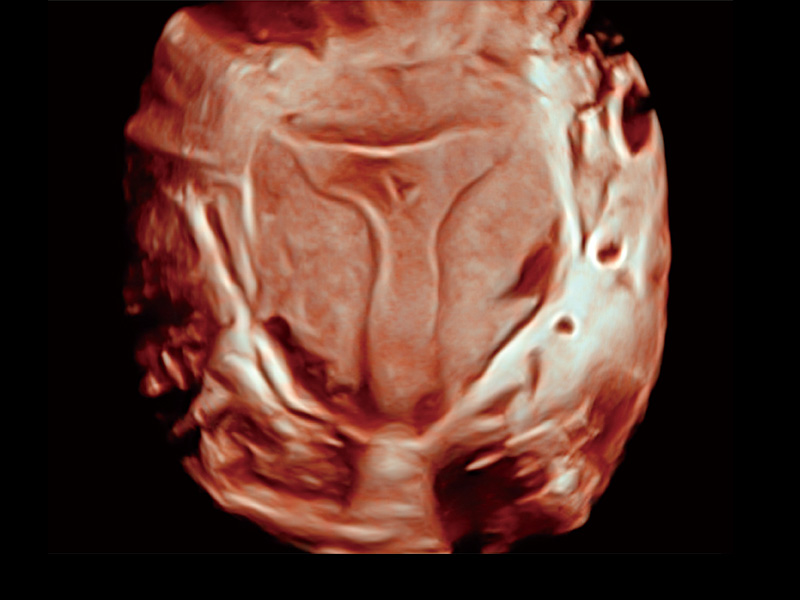

中央型宫腔粘连